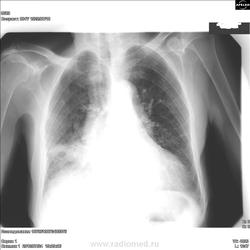

Заканчивался рабочий день.Бабушка с большой грыжй на животе,прямой снимок "лицом к трубке".

Очень даже ателектаз.

Ателнктаз.А отчего?

Предположительно, нарушение проходимости нижнедолевого и среднедолевого бронхов. Причину точно указать трудно. Постройте диффряд.

Раньше это называли Синдром средней доли,имея в виду-ателектаз,цирроз,пневмонию,туберкулез,рак.\нижняя доля не при делах\В соответствии с этим определялись с тактикой.

Среднюю долю показательнее резать на боку. Насчет полости распада: она есть (в прямой проекции - явно, в боковой  - с уровнем/черные стрелки, или может ниже/красные стрелки).